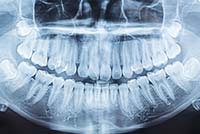

LEISTUNGSSPEKTRUM

Wir bieten Ihnen ein breites Spektrum an Diagnose- und Therapieverfahren an, um Sie zahnmedizinisch und -prophylaktisch rundum professionell und nachhaltig zu versorgen.

LEISTUNGEN IM DETAIL

- Zahnextraktionen

- Implantationen

- Operative Entfernung von Zähnen

- Weisheitszahnentfernung

- Entfernung von Zysten

- Wurzelspitzenresektionen

- Chirurgische Entfernung von kleinen Tumoren